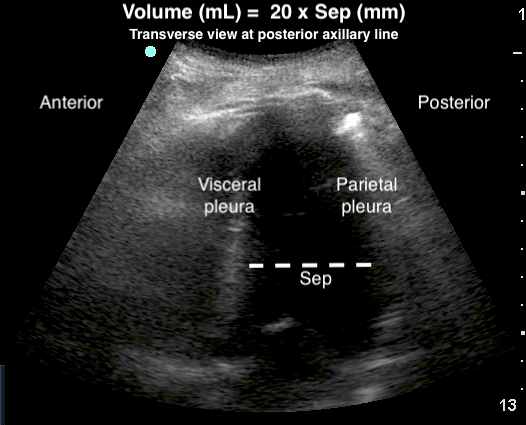

- Volume of the effusion can be measured,28,83-85 more effectively than with CXR.28 A quick and easy method uses the largest distance between parietal and visceral pleura at end-expiration.83

- Figure 21. Estimation of pleural effusion volume